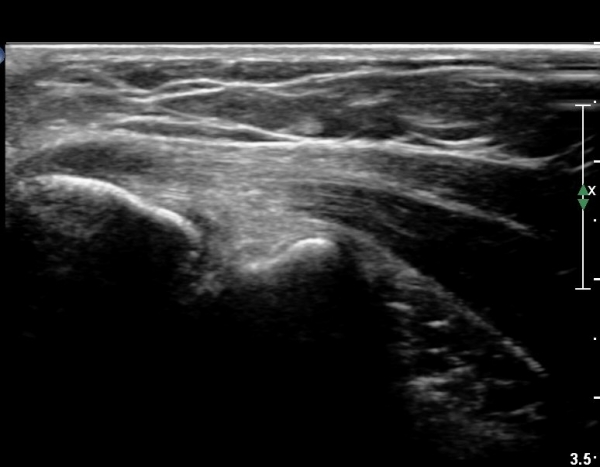

º´º¯ ºÎÀ§·Î ŽÃËÀÚ¸¦ À̵¿ÇÏ±â °Ç ºÎÂøºÎ Àú¿¡ÄÚ º¯¼ºÀÌ ¶Ñ·ÈÇÏ´Ù(±×¸² 5).

ÃÊÀ½ÆÄÀ¯µµÇÏ ÁÖ»çÄ¡·á »çÁøÀ¸·Î ¹Ù´ÃÀÌ º´º¯ ºÎÀ§¿¡ Á¤È®È÷ À§Çϰí ÀÖ´Â °ÍÀÌ º¸ÀδÙ(»çÁø 6).

Áֻ縦 ½ÃÇàÇÏ´Ï ÁÖ»ç¾×ÀÌ ¸¶Ä¡ ³¶Á¾¿¡ ÁÖ»çÇÏ´Â °Íó·³ ÁÖ»çµÇ¾î Àú¿¡ÄÚ º´º¯ ºÎÀ§°¡

ÆÄ¿­µÈ °ÍÀÓÀÌ È®ÀεȴÙ(÷ºÎ µ¿¿µ»ó).